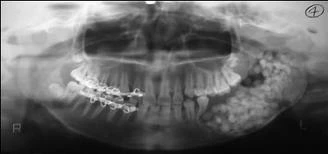

Hình 9D. Mũi tên đen chỉ vào răng nanh hàm dưới hoàn toàn nằm ngoài cung hàm và có thể bị nhổ bỏ như là một phần của kế hoạch điều trị chỉnh nha, mũi tên trắng chỉ vào một răng cối nhỏ thứ hai hàm trên bị sâu răng nghiêm trọng